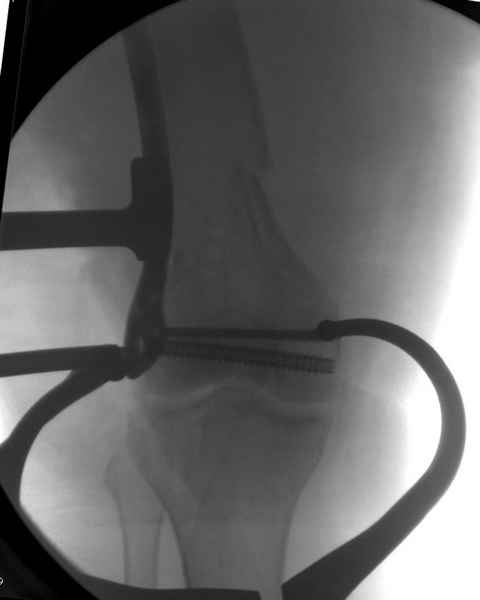

При наличии различных имплантов, любые варианты: слева (полу) открытым - мининвазивным, а справа закрытым интрамедуллярным методом, его считаем более чем приемлемым для фиксации данных переломов.

Проксимальная и дистальная блокировка, независимо от техники введения штифта, ретроградно или антеградно, гарантирует сращение сегментарных переломов бедра без укорочения. Штифты диаметром 12 мм с блокировкой сверху и вниз двумя шурупами выдерживают вес 75 кг больного, что позволяет раннюю профилактику контрактур.

Погоня за "красивой рентгенограммой" не всегда оправдана для фиксации кости, где имеется массивное мягкотканое покрытие. Если так уж хочется исправить положение кости, то при наличии ЭОП, большие костные фрагменты могут быть развернуты или приближены к основному фрагменту методом применения Joystick.

Главное в лечении сегментарных переломов - необходима осторожность при рассверливании канала, продвижение гибкого сверло через сегмент проводят без сверления, толканием, а то были случаи, когда весь сегмент крутился вместе со сверлом.

Из-за вариабельности установки дистальных шурупов и возможности перкутанного введения проксимально предпочитаем DePuy Polyax, хотя на сегодняшнем маркете множеств вариантов фиксации дистального бедра перкутанном методом.